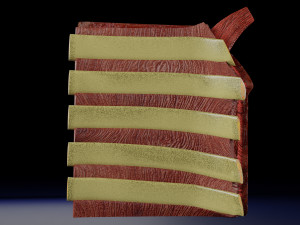

This is a 1:1 scaled model of right breast cut opened in sagittal plane to reveal its internal antomy and histology (schematic). The deeper parts and fascial layers are also depicted to give a very detailed approach to the model. The full layers starting from skin, nipple areola, till intercodtal muscles and ribs are also depicted.